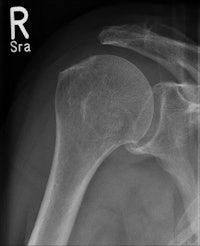

Data from 474 CR skeletal exams were collected; the CR cassette was then traded out for the wireless flat-panel DRX-1 detector to acquire an identical mix of 467 skeletal x-ray procedures. More than 50 patients were examined for each of nine types of inpatient and outpatient skeletal studies performed from January to June 2010.

Lehnert and colleagues also found that image quality also significantly improved in the shift from skeletal CR to DRX-1. Those results will be described in a separate study.